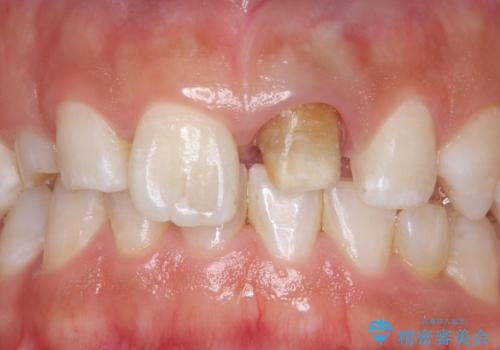

変色した前歯 ジルコニアクラウンでの修復

- 前歯の変色を主訴に来院された患者様です。

根管治療からのやり直しをした後、ジルコニアクラウンで色調の改善をしていきます。

歯の黒ずみを完全に見えなくすることができ、大変喜んでいただけました。

被せ物を装着する際は、歯の中(根管)から綺麗にすることも重要となります。